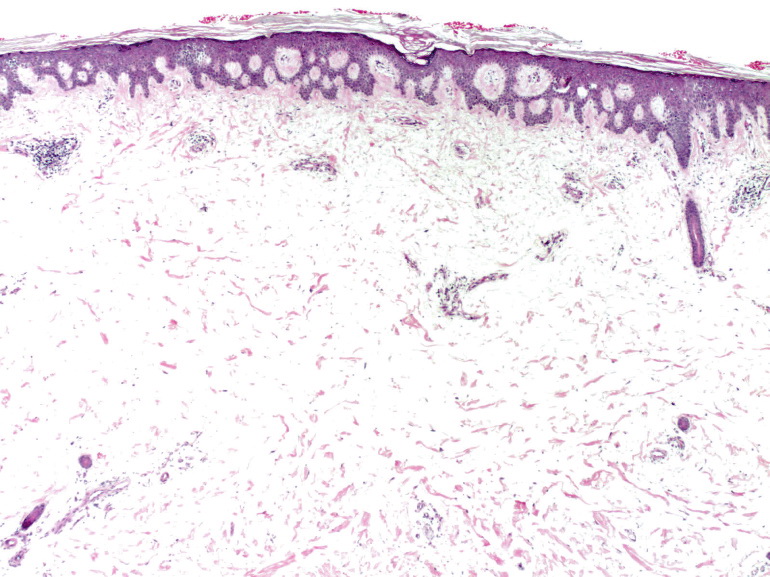

Myxoedema =الوذمة المخاطية